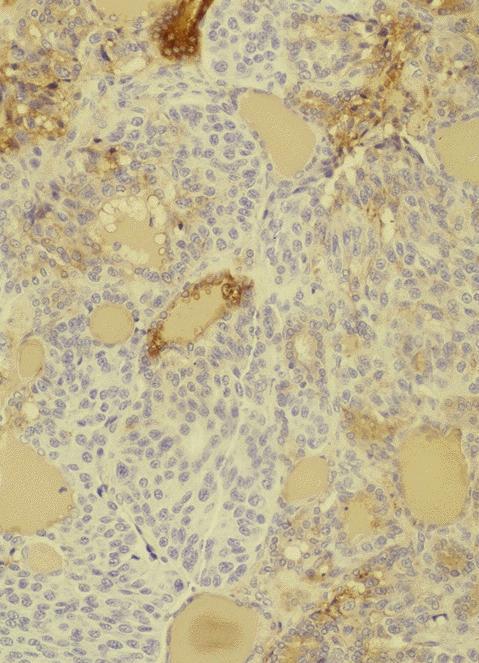

Microscopic (histologic) description

- Wide variety of morphology, can mimic any other thyroid malignancy

- Round, plasmacytoid, polygonal or spindle cells in nests, cords or follicles; often mixtures of these cells

- Round nuclei with finely stippled to coarsely clumped chromatin and indistinct nucleoli, occasional nuclear pseudoinclusion

- Eosinophilic to amphophilic granular cytoplasm due to secretory granules

- Generally low mitotic figures

- Stroma has amyloid deposits from calcitonin, prominent vascularity with glomeruloid configuration or long cords of vessels (Am J Surg Pathol 1995;19:642), coarse calcifications, occasional psammoma-like bodies

- Mucin in 42% (Arch Pathol Lab Med 1983;107:70)

- Often angiolymphatic invasion

- Occasionally marked neutrophilic infiltrate, oncocytic tumor cells, papillary patterns

- May entrap follicles

- C cell hyperplasia present in familial but not sporadic cases

Microscopic (histologic) images

Contributed by Shuanzeng Wei, M.D., Ph.D., Joseph Christopher Castillo, M.D. and Mark R. Wick, M.D.